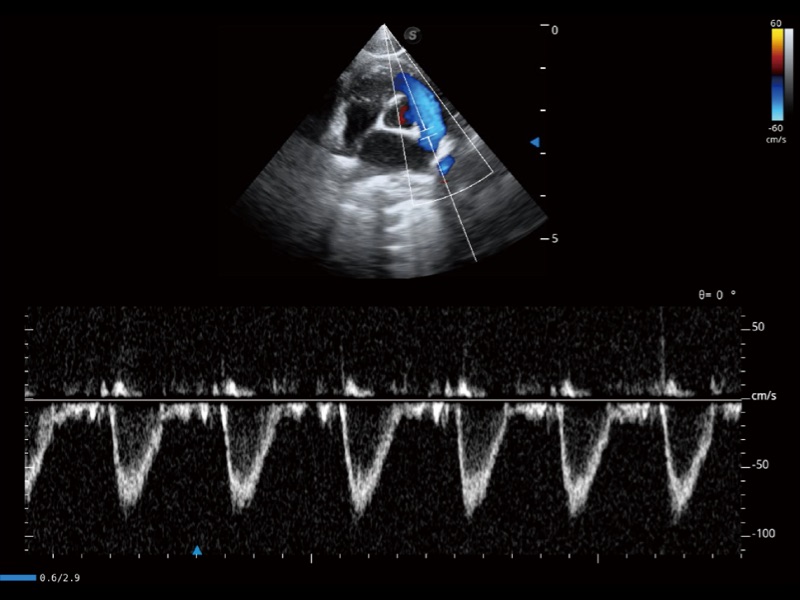

通過(guò)360度任意調(diào)節(jié)3條M型取樣線,在同一心動(dòng)周期上觀察心臟不同位置的運(yùn)動(dòng)曲線,得到準(zhǔn)確的心功能測(cè)量數(shù)據(jù),有效評(píng)估心肌運(yùn)動(dòng)及左心室功能。

能夠基于左心室壁追蹤和辛普森法,自動(dòng)計(jì)算射血分?jǐn)?shù),支持多個(gè)可移動(dòng)點(diǎn)描跡,與手動(dòng)測(cè)量相比,極大節(jié)省了動(dòng)物醫(yī)生的時(shí)間和精力。